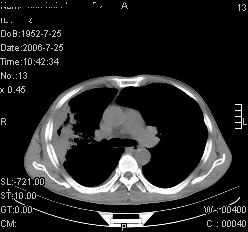

患者,男,54岁,咳嗦,咳痰20天。抗炎治疗2周。现esr76mm/h,目前患者症状明显好转,但发现两次ct片未见明显变化。两次分别做与7.25、7.31。第一次诊断右肺上叶炎症累计胸膜。大家看,从影像上内排除结核吗?

结核的可能性非常大,右上肺病变应该考虑干酪性肺炎。理由:

1.纵隔内多发淋巴结肿大。

2.esr76mm/h。

3.虽经抗炎治疗肺窗病灶有所吸收、减小,但纵隔窗病灶形态、密度、范围无明显变化。如果是单纯的大叶性肺炎,“抗炎治疗2周,目前患者症状明显好转”病灶应该基本消散了,至少也处于吸收消散期,密度变淡、范围变小。同时本病例所示其内的密度不均匀,见多发大小不一空洞样影也不符合大叶性肺炎吸收消散期表现。

病灶特点:片状 索条 结节混杂影,部分融合,密度不均,广泛累及相应胸膜.

临床治疗;二周未吸收.但症状好转.

多考虑:肺结核.